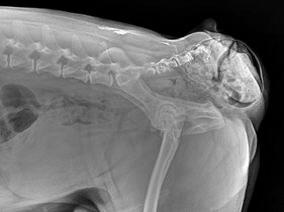

DR指在计算机控制下直接进行数字化X线摄影的一种新技术,即采非晶硅平板探测器把穿透人体的X线信息转化为数字信号,并由计算机重建图像及进行一系列的图像后处理。DR系统主要包括X线发生装置、直接转换平板探测器、系统控制器、影像监示器、影像处理工作站等几部分组成。DR由于采用数字技术,因此可以根据临床需要进行各种图像后处理,如图像自动处理技术,边缘增强清晰技术、放大漫游、图像拼接、兴趣区窗宽窗位调节以及距离、面积、密度测量等丰富的功能。另外由于DR技术动态范围广,X线光量子检出效能(DQE)高,具有很宽的曝光宽容度,即使曝光条件稍差,也能获得很好的图像。DR的出现打破了传统X线图像的观念,实现了人们梦寐以求的由模拟X线图像向数字化X线图像的转变,与CR(Computed Radiography)系统比较具有更大的优越性。

医用x光机与ar机区别在于传统医用x光机拍完片子之后不可以将图像直接显示在屏幕上,需要胶卷才可以显示。从拍摄到出胶卷的时间间隔比较长。而ar机则是一种数字化高频智能x光机,DR机用矩阵直接代替了胶卷的功能,拍完就可以显示在电脑显示器上,这一优点大大节省了一声诊断的时间。其次,从成像效果上看,医用X光机与DR机也是有区别的,医用x光机在拍摄过程中信号有所损失,而DR机的成像效果更加清晰。DR机无需耗材,一次投入,终身受益。因此,现在各级医院更加青睐于DR机,逐渐淘汰传统医用x光机。

现在普遍应用的DR主要是采用平板探测口(FPD)对X线产生的图像信号进行扫描和直接读出,成像原理是先将X线信号转变为可见光通过光电2极管组成的藻膜层(TFT)进行聚集,由专门的读出电路直接读出送计算机系统进行处理。目前平板探测口分为以非晶硅为代表的间接转换数字摄影(IDDR)和以非晶硒为代表的直接转换数字摄影(DDR)两种类型。

DR的组成一般包括高压发生器、X线球管及支架、平板探测口、系统控制口等构成。与常规X线信号相比,优点除了具有CR的优点外,DR系统是用平板探测的X线接收装置替代了传统的增感屏及胶片,实现了X线信号的数字化,信号的动态范围、空间的分辨率及密度分辨率高,曝光剂量低,可随时得到供医生观看的X射线影像。在影像传输、存储和放大等处理中几乎不损失影像质量,成像速度远快于传统的胶片X射线系统。